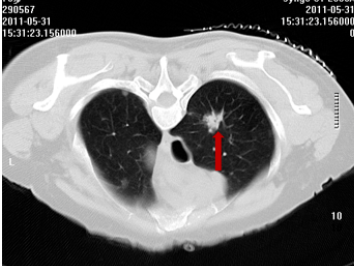

2011年,一名70岁患者因出现咳嗽、咳痰带血等症状就诊于我院呼吸门诊,在完善CT等相关检查后,患者被诊断为右上腺癌(多原发),在充分的与患者及家属进行沟通后,明确表示不接受外科手术,科室为患者制定并实施了CT引导下经皮肺穿刺射频消融+碘125粒子植入放疗+化疗的治疗方案。

术 前

术 后

患者分别在治疗4月和1年后复查胸部CT显示病灶稳定,病情得到进一步控制。